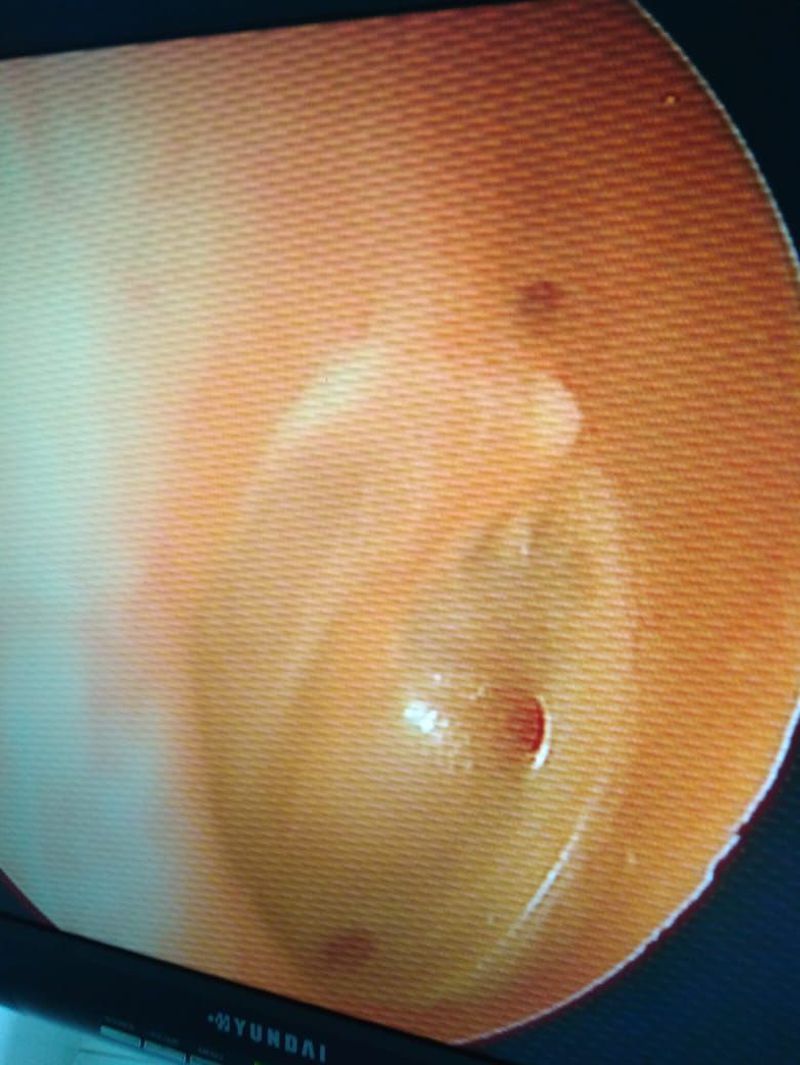

A male 32 years old, come to hospital with complaints othorea right ear since 7 months and decrease hearing in right ear since 5 months. The discharge was scanty, yellow and mukoid. He also had history of upper respiration infection and fever. On otoscopic examination of right ear there are multiple perforation, wet and the external auditory canal filled with discharge. The otoendoscopy examination can you see the picture. The left ear was found to be normal. What is the diagnosis? Type of tympanic membran perforation ? Treatment ?